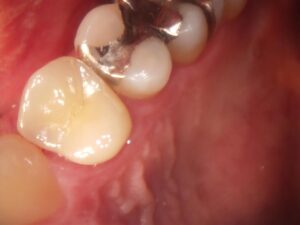

長く使用した被せ物は、経年劣化により変色や欠けたりすることがあります。

被せ直しをすることでより綺麗に、美しく仕上げることができます。

気になる方はスタッフまでお問い合わせください!